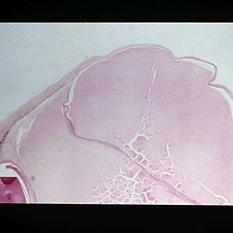

Slide 12-1

Feb 26 2019 by Lancaster Course in Ophthalmology

Congenital glaucoma. Anterior chamber angle from a 2-year-old child with congenital glaucoma is cut tangentially and resembles the configuration seen normally in a fetus (H&E xlOl).

Condition/keywords: congenital glaucoma